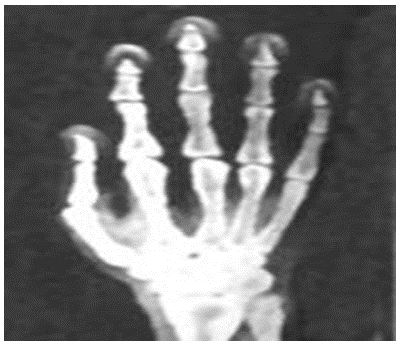

Question. The figure shows an X-ray photograph of the human hand. Which of these statements about X-rays is likely to be true?

(a) They can pass through human bones.

(b) They can pass through muscles but not bones.

(c) They make the human body translucent.

(d) They absorb light from the human body.

Answer : B